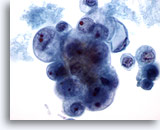

Figure 28: Breast FNA, Ductal carcinoma in situ. This is a cellular aspirate showing clusters of tumor cells, single malignant cells and foamy macrophages. Ductal carcinoma in situ (DCIS) often shows myoepithelial cells overlying the malignant cell clusters. Tumor cells tend to be clustered rather than single as in invasive tumor. In addition, tubular structures are not associated with DCIS. Comedo DCIS is characteristically associated with necrosis and calcium. 40x

Figure 28

Breast FNA, Ductal carcinoma in situ.

This is a cellular aspirate showing clusters of tumor cells, single malignant cells and foamy macrophages. Ductal carcinoma in situ (DCIS) often shows myoepithelial cells overlying the malignant cell clusters. Tumor cells tend to be clustered rather than single as in invasive tumor. In addition, tubular structures are not associated with DCIS. Comedo DCIS is characteristically associated with necrosis and calcium.

40x